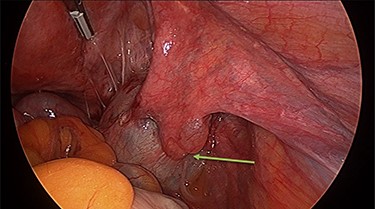

Operation findings consisted of left hydrosalpinx and para-tubal cyst adhered to pouch of douglas, with the left tube torted 3 times (Figs 4 and 5). There was a 5-cm para-tubal cyst on the right tube adhered to right side of pelvis/rectum/pouch of douglas (Fig. 6). The ovaries appeared normal.

Right para-tubal cyst, implanted to the pouch of Douglas and right ovarian fossa.